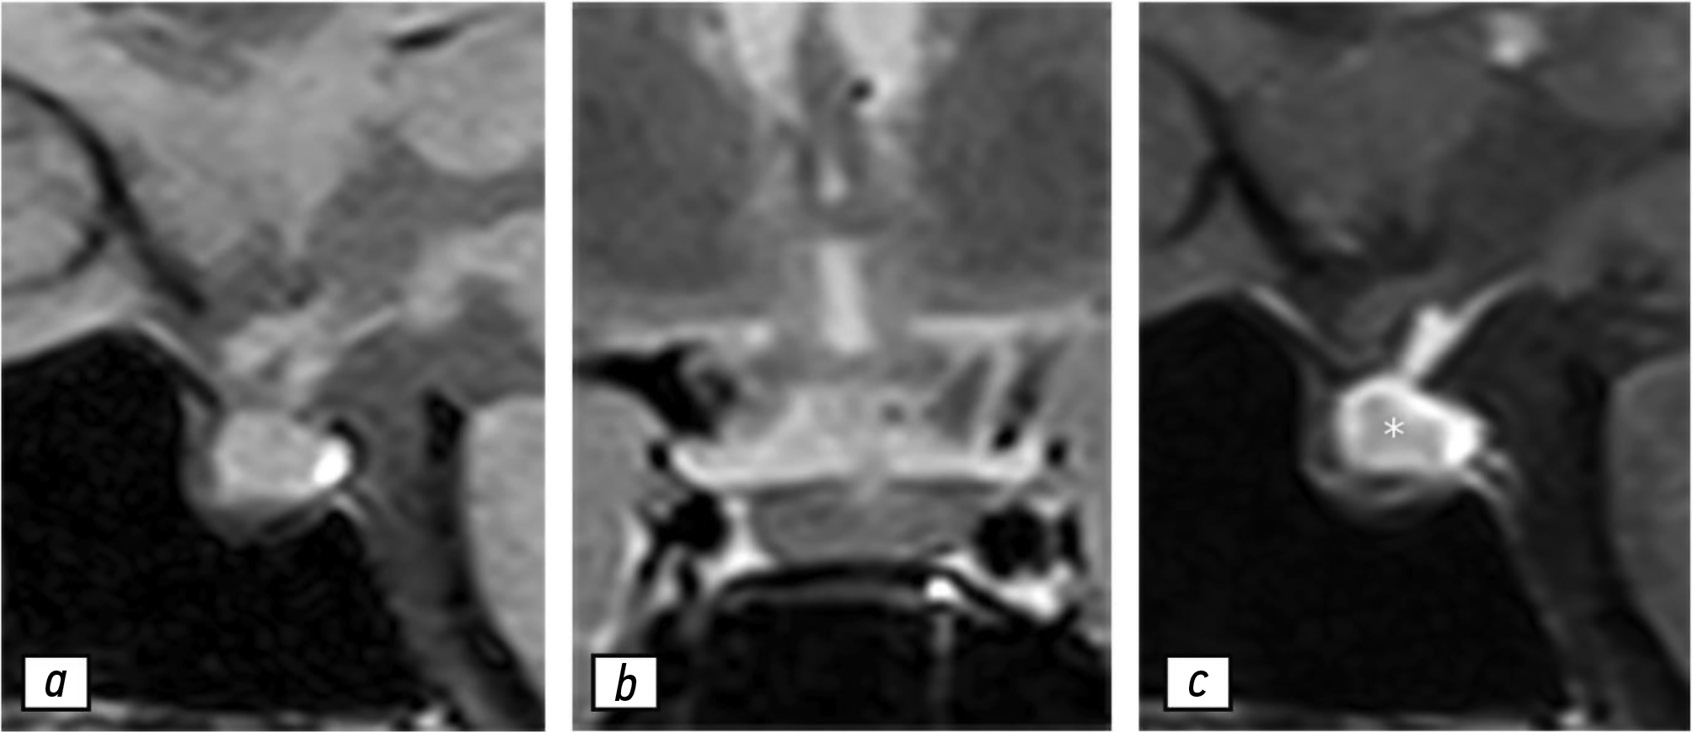

Autoimmune hypophysitis: a case of follow-up during the COVID-19 pandemic period

Hypophysitis is a rare inflammatory disorder that affects the pituitary gland and infundibulum, stems from autoimmune, infiltrative, infectious, or unknown causes. Its clinical diagnosis can be challenging because several pituitary lesions, including adenomas and metastases, may clinically present with similar characteristics. Magnetic resonance imaging is crucial for diagnosing suspected cases of hypophysitis and categorizing them as adenohypophysitis (anterior pituitary gland involvement) or infundibulo-neurohypophysitis (pituitary stalk and posterior pituitary involvement). Hypophysitis can be categorized as primary (autoimmune) or secondary due to local lesions (e.g., granulomas, cysts, adenomas) or systemic diseases (e.g., sarcoidosis, Wegener’s granulomatosis). Different factors may have impact on clinical course of hypophysitis. Among them background treatment. These cases have not been sufficiently studied and are practically not presented in publications.

A 37-year-old female with a history of hyperprolactinemia was being treated symptomatically with cabergoline. At first magnetic resonance imaging heterogeneity of the hypophysis was revealed. In September 2021 the follow-up magnetic resonance imaging revealed an increase in the size and heterogeneity of the pituitary gland. In December 2021, the patient developed severe COVID-19-associated pneumonia and was treated with corticosteroids and oxygen support. In May 2022 magnetic resonance imaging revealed a marked increase in the size and heterogeneity of the pituitary gland. Significant clinical and radiological improvement were stated after adding prednisone (10 mg in the morning and 5 mg in the evening) to her treatment.

The patient was followed-up during the COVID-19 pandemic. The management and imaging studies of such patients may be tricky due to the effects related to COVID-19 and its treatment.

During monitoring of hypophysitis, physicians should consider the impact of COVID-19 treatment, particularly corticosteroid therapy, when evaluating the radiological changes.